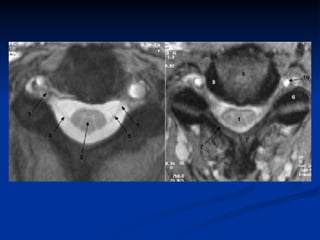

IRM cervicale Technique « Scowt view » Séquence sagittale TSE T2 Séquence sagittale TSE T1 Coupe axiale EG T2 Séquence EG à effet myélographique Injection de PC non systématique

IRM cervicale Technique« Scowt view » Séquence sagittale TSE T2 Séquence sagittale TSE T1 Coupe axiale EG T2 Séquence EG à effet myélographique Injection de PC non systématique